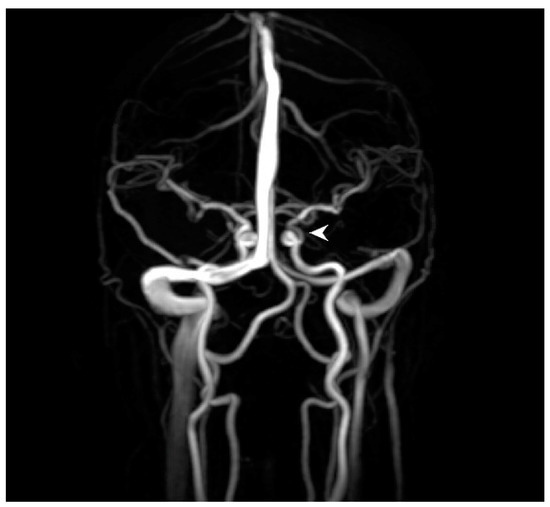

Ophthalmology was consulted after the vision changes did not resolve with 1000 mg of acetaminophen. Visual acuity was 20/20 in the right eye and 20/30 in the left eye. Pupils were equal, round, and reactive to light without relative afferent pupillary defect. Intraocular pressure was 10 mmHg in both eyes. Confrontational visual fields (via counting fingers) were normal in the right eye and revealed a superonasal defect in the left eye. Funduscopic exam of the right eye was normal, but in the left eye, there was frank whitening of the inferior half of the retina and a visible yellow refractile body within the inferior arterial arcade at the disc margin. Branches of the retinal artery downstream from this plaque were narrowed/attenuated (Figure 2). She was diagnosed with branch retinal artery occlusion (BRAO).

Figure 2. Color fundus photograph of the left eye at presentation shows retinal whitening of the inferior fundus consistent with diagnosis of branch retinal artery occlusion. Note the yellow refractile body within the inferior arterial arcade at the disc margin (arrow) and attenuation of peripheral arterioles (arrowheads).